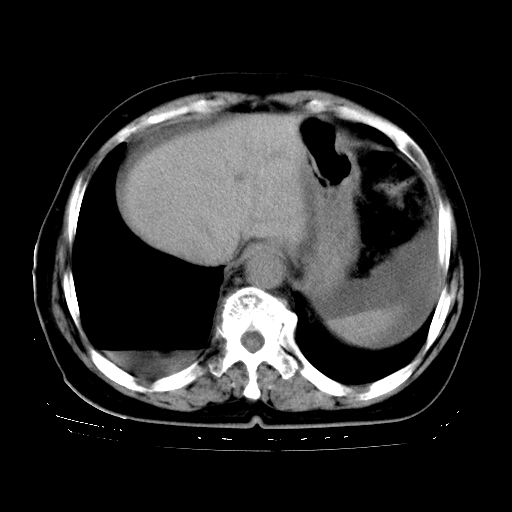

以下是引用zhangzhongshou在2008-3-22 12:52:00的发言:[br]1、右侧液气胸。[br]2、腹水。建议进一步检查。

以下是引用鲁巨ct在2008-3-22 14:10:00的发言:[br]1、右侧液气胸,右中下叶节段性不张。[br]2、腹水,建议上腹部ct检查

以下是引用zjzjr在2008-3-22 17:19:00的发言:[br]1、右侧液气胸,右下叶节段性不张。[br]2、腹水,建议上腹部ct检查